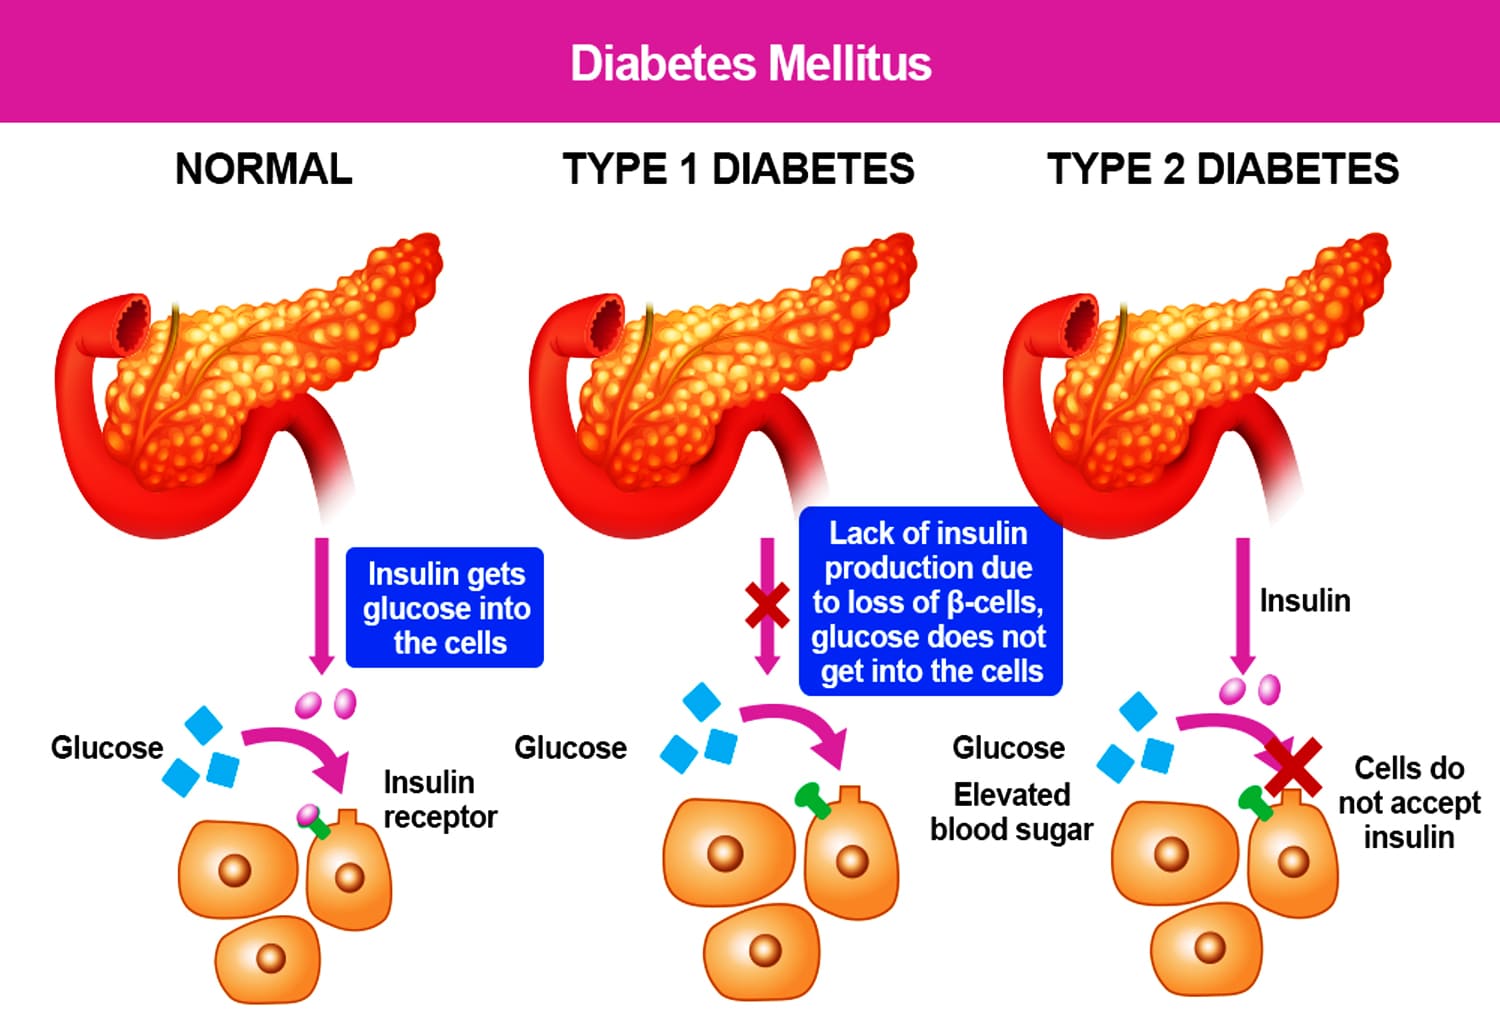

Bekam Pre Diabetes & Diabetes Tipe 1 & Tipe 2

Gejala diabetes tipe 1 dan tipe 2 hampir serupa.

Kondisi metabolik seperti diabetes memerlukan perhatian dan pengelolaan yang konsisten. Gejala yang sering dirasakan antara lain mudah lelah, perubahan berat badan, dan gangguan kadar gula.